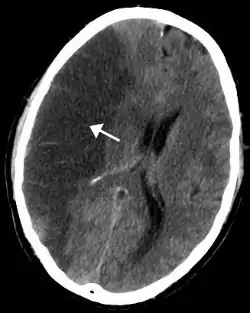

![]() Billede fra CT-scanning af patient med infarkt i Arteria media cerebri. | |

Diagnosen stilles ud fra en klinisk undersøgelse, men det er ikke muligt at skelne mellem en blodprop og en blødning på baggrund af denne.[2] Som supplement til den kliniske undersøgelse vil der næsten altid udføres en CT-scanning eller MR-scanning. Formålet med disse scanninger er at understøtte diagnosen, vurdere prognosen og udelukke differentialdiagnoser, f.eks. tumor/metastaser, subaraknoidal blødning (SAH) og subduralt hæmatom (SDH).

Inden man begynder behandlingen, skal man have afklaret om apopleksien skyldes en blodprop eller en hjerneblødning. Dette kan gøres ved en CT-scanning eller en MR-scanning. Ved en CT-scanning kan man i begyndelsen kun se forandringer, hvis der er tale om en blødning, mens man ved en MR-scanning kan se forandringerne i alle tilfælde.